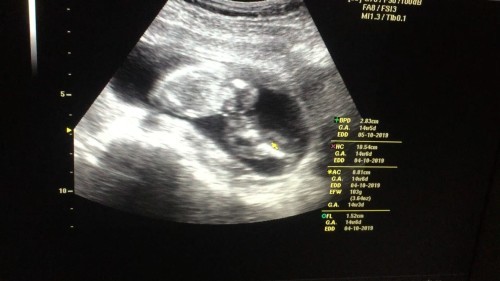

พอดีวันที่ 13 นี้หมอนัดค่ะ อายุครรภ์วันที่นัดก็ประมาณ 13+4 วีค อยากเห็นภาพอัลตร้าซาวด์ของแม่ๆที่อายุครรภ์เท่ากันหรือใกล้เคียงกันค่ะ ว่าน้องมีพัฒนาการถึงไหนแล้ว ?

13weekค่ะ

13wค่ะ

13+2ค่ะ